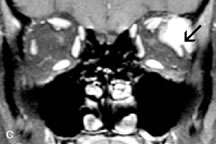

Muscle Disorders

Extraocular muscle enlargement in patients with thyroid-associated orbitopathy is demonstrated equally well with CT and MRI studies. However, the superior tissue contrast on MR images reveals better details of the relationships of the optic nerve to the thickened muscles at the orbital apex (Fig. 16).50 In addition, MRI may be able to differentiate between muscles that are enlarged as a result of edema and active inflammation and those enlarged because of fibrosis by their T2 relaxation times.21 Quantitative MRI was not found to be accurate in predicting the success of low-dose orbital irradiation.51 However, a muscular index relating the diameters of the rectus muscles to the bony orbital dimensions was useful in predicting optic nerve compression.52

Fig. 16. A-C, T1-weighted MR scans obtained with a high-resolution surface coil demonstrate fusiform enlargement of the extraocular muscles. The medial, lateral, and inferior rectus muscles are especially involved. Note the relative sparing of the tendinous insertions, a finding characteristic of this disease process, as well as fatty infiltration of the lateral and inferior rectus muscles. There is marked proptosis, best visualized on the sagittal image (A), and mild crowding of the optic nerve at the orbital apex.

MRI is also effective in imaging orbital tumors of mesenchymal origin, such as rhabdomyosarcoma, particularly in the assessment of extension into the anterior and middle cranial fossae (Fig. 17).37 The lack of any pathognomonic radiologic features necessitates rapid orbital biopsy when rhabdomyosarcoma is suspected.

Fig. 17. A. T1- and (B) T2-weighted MR scans demonstrate a preseptal and extraconal mass displacing the globe medially. The mass is slightly hyperintense on the T1-weighted scan and very hyperintense on the T2-weighted scan owing to the high extracellular water content of the neoplasm. The lesion abuts the globe and appears to infiltrate the lateral rectus muscle (arrow). C and D. Postcontrast fat-suppressed T1-weighted scans demonstrate intense enhancement of the highly infiltrative lesion that is invading the lateral rectus, superior rectus, and levator palpebrac superioris muscle (double arrows).